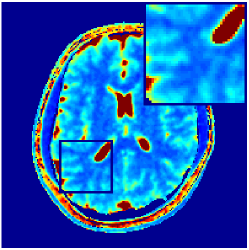

Two sets of experiments were conducted here: first, we used the 2D and 3D acquisition sequences for scanning a healthy volunteer’s brain (real-world acquisitions). Figures 6 and 7 display the parametric maps reconstructed from 2D spiral and radial readouts. We computed the T1, T2 and proton density (PD) maps using baseline reconstruction algorithms ZF, VS, LR, FLOR, AIR-MRF and our proposed LRTV. While baselines use DM either for quantitative inference or also during reconstruction (i.e. AIR-MRF), we further compare the DM-free LRTV’s performance when cascaded to DM, KM and MRFResnet for quantitative inference. For the 3D spiral acquisitions we compared LRTV and its closest competitor VS in Figure 8. Outcomes from other tested algorithm are displayed in the supplementary materials (Figure S5). Since FLOR does not use dimensionality-reduction, our system ran out of memory during 3D reconstruction; hence results are not reported in this case.

VI-E1 Discussion

The LRTV-DM and LRTV-MRFResnet perform on par, and both outperform all tested baselines for reconstructing T1, T2 and PD maps in all acquisition schemes. This can be observed both visually in Figures 6, 7, 8, S2 and S3, and quantitatively in Table IV across all tested metrics. Other baselines were unable to successfully remove the under-sampling artefacts in TSMIs, and these errors propagated to the parameter inference phase and resulted in inaccurate maps. Temporal-only priors incorporated within LR are shown insufficient to regularise the inverse problem and LR sometimes (e.g. 2D spiral acquisitions) can admit solutions with even stronger artefacts than the model-free ZF baseline. This issue was previously studied for other non-Cartesian MRF readouts that similar to our spiral/radial trajectories, miss to sample the corners of the k-space in all timeframes (see section 2.2.2 and figure 2 in [19]). In the absence of reference for the k-space corners information, the LR iterations despite minimising the objective can converge to solutions with high-frequency artefacts, as visible in the computed maps. This highlights the need for adding an appropriate spatial-domain regularisation. FLOR reduces the LR’s artefacts but this improvement is limited because the suggested nuclear norm penalty does not incorporate an explicit spatial regularisation. Further for reducing artefacts, FLOR can introduce an undesirable bias in the computed T1/T2 maps e.g. see error maps in Figures S2 and S3. The non model-based VS baseline incorporates spatial regularisation and results in spatially smoother maps than ZF and LR, but it is unable to output artefact-free images. Further and consistent with our in-vitro experiment, we observe that VS overestimates the T2 values (e.g. in White and Grey matter regions) in tested 2D acquisitions i.e. the spatial regularisation trades off agains the quantification accuracy. The model-based AIR-MRF adds spatial regularisation through 2D/3D low-pass Gaussian filters however this trades off the sharpness of the computed maps and can increase the errors at the tissue boundaries (we searched Gaussian spreads that keep the blurs and high-frequency artefacts minimal). For our acquisition readouts, Gaussian filters performed better than disk filters of [19] for avoiding strong Gibbs artefacts. On the other hand, the spatiotemporally regularised LRTV greatly improves the TSMI reconstructions i.e. 4 dB enhancement compared to the closest competitor baseline (Table IV). This enables computing accurate and aliased-free multi-parametric inference using DM or the DM-free learning-based alternative MRFResnet as visible in Figures 6, 7, 8, S2 and S3. MRResnet and DM score competitive quantitative inference results i.e. T1 and T2 MAPE less than 5% and 9%, respectively (Table IV). KM also outputs comparably accurate T1 maps, however this shallow learning model despite having a model size larger than MRFResnet, is unable to learn accurate T2/PD quantification and it results in poor estimated maps, consistent with our observations in section VI-C.